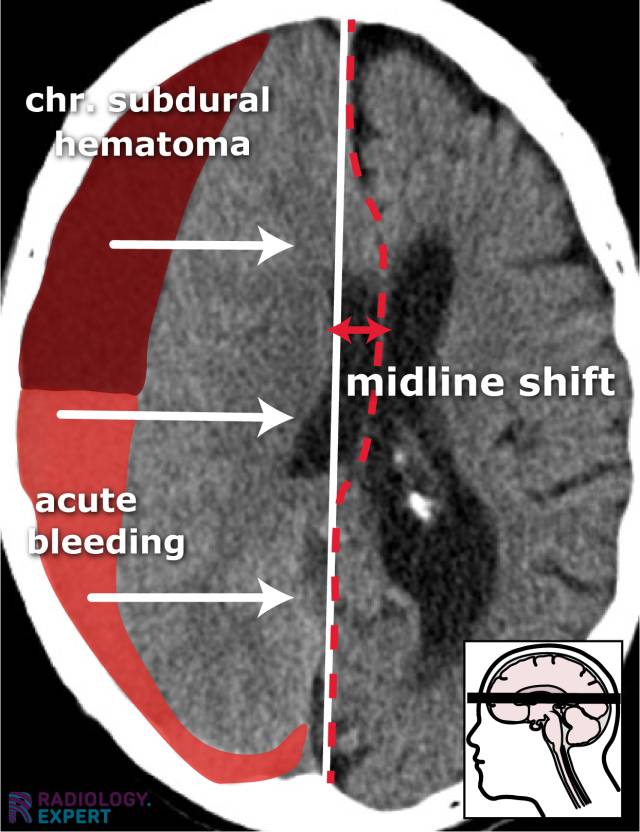

From www.radiology.expert

CT brain hemorrhage What Is A Midline Shift Of The Brain Especially for operating on a mass or lesion or evacuating brain hematoma. Midline shift refers to a shift (displacement) of brain tissue across the centre line of the brain. Midline shift describes the situation where the midline of the intracranial anatomy is no longer in the midline and is the result of pushing or pulling forces within. It may occur. What Is A Midline Shift Of The Brain.